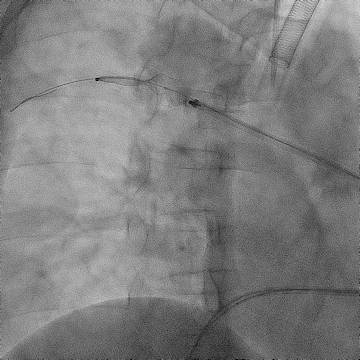

手术过程(二):

使用“Wire In Plug” 技术:在体外释放 20 mm AVP Ⅱ (网盘不解锁),使用穿刺针配合stiff导丝穿过三个网盘,回收至鞘内。

图片